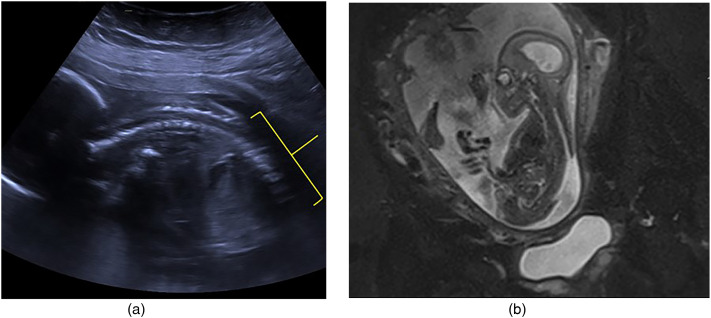

Discussion: In our unit, we use NovoSorb Biodegradable Temporising Matrix to reconstruct full-thickness skin and soft tissue defects. It is a synthetic, biodegradable, dermal regeneration template, composed of polyurethane foam bonded to a transparent sealing membrane and typically requires a two stage reconstruction. Integration and vascularisation take approximately three weeks. After this time, the recipient wound bed is suitable for split thickness skin grafting. A further benefit of dermal regeneration templates is the possibility of 'stacking' layers, which serves to increase the thickness of the final construct and to minimise overall contour defects. The authors present the case of a one-day-old full-term neonate with a large lumbosacral myelomeningocele that was successfully managed with staged, stacked NovoSorb Biodegradable Temporising Matrix and split thickness skin grafting. The authors believe this is the first case in which a 'stacked' dermal regeneration templates has been used to achieve healing of a primary myelomeningocele defect.

Lay summary: Background: NovoSorb Biodegradable Temporising Matrix (BTM) is a dermal regeneration template (DRT) and is used to reconstruct wounds following full-thickness skin and soft tissue loss resulting from burn injury, trauma, infection or surgery. It is composed of 2-millimetre thick, synthetic, biodegradable polyurethane foam bonded to a transparent (non-biodegradable) sealing membrane. Like all DRTs, it acts as a scaffold for cellular integration and vascularisation to eventually form a 'neo-dermis'. This is usually apparent from around three weeks. A second stage procedure can then be performed, with removal of the outer sealing membrane and split thickness skin grafting of the vascularised layer.Objectives: Myelomeningocele is a severe and complex congenital malformation of the central nervous system and forms the group of anomalies commonly referred to as neural tube defects (NTDs). Neural tube closure usually occurs at around four weeks of gestation and failure to do so, results in an open communication between the neural placode and the external environment. The degree of functional impairment varies but can include: lower limb paralysis; sensory loss; bladder and bowel dysfunction. In order to preserve neural function and minimise the risk of infection, surgery is usually required to close the defect. Reconstruction is varied and is dependent upon the site and size of the defect as well as the quality of the surrounding soft tissues. The use of local flaps has the potential complication of skin necrosis. Muscle based flaps may be debilitating and limit future functionality and worsen postural development. We were presented with a one-day-old neonate with a large lumbosacral myelomeningocele. A DRT (NovoSorb BTM) was selected as the primary reconstruction. Firstly, selection provided relatively low risk, with minimal morbidity and preserved the full complement of flap based reconstructive options for a later stage should instrumentation be required. Secondly, NovoSorb BTM conferred a robust seal over the dural repair with no demonstrable cerebrospinal fluid leak. Thirdly, the ability to add layers ('stack') of NovoSorb BTM in stages, once integration and vascularisation of the previous layer is complete, allows reconstruction of deeper contour defects.Discussion: We have illustrated the successful use of NovoSorb BTM as a DRT to achieve closure of a large lumbosacral myelomeningocele without complication and with longstanding stability. We believe this technique provides reconstructive teams with an alternative option that is effective, safe and reproducible and which spares local tissues for future elective reconstructive procedures, should they be required.